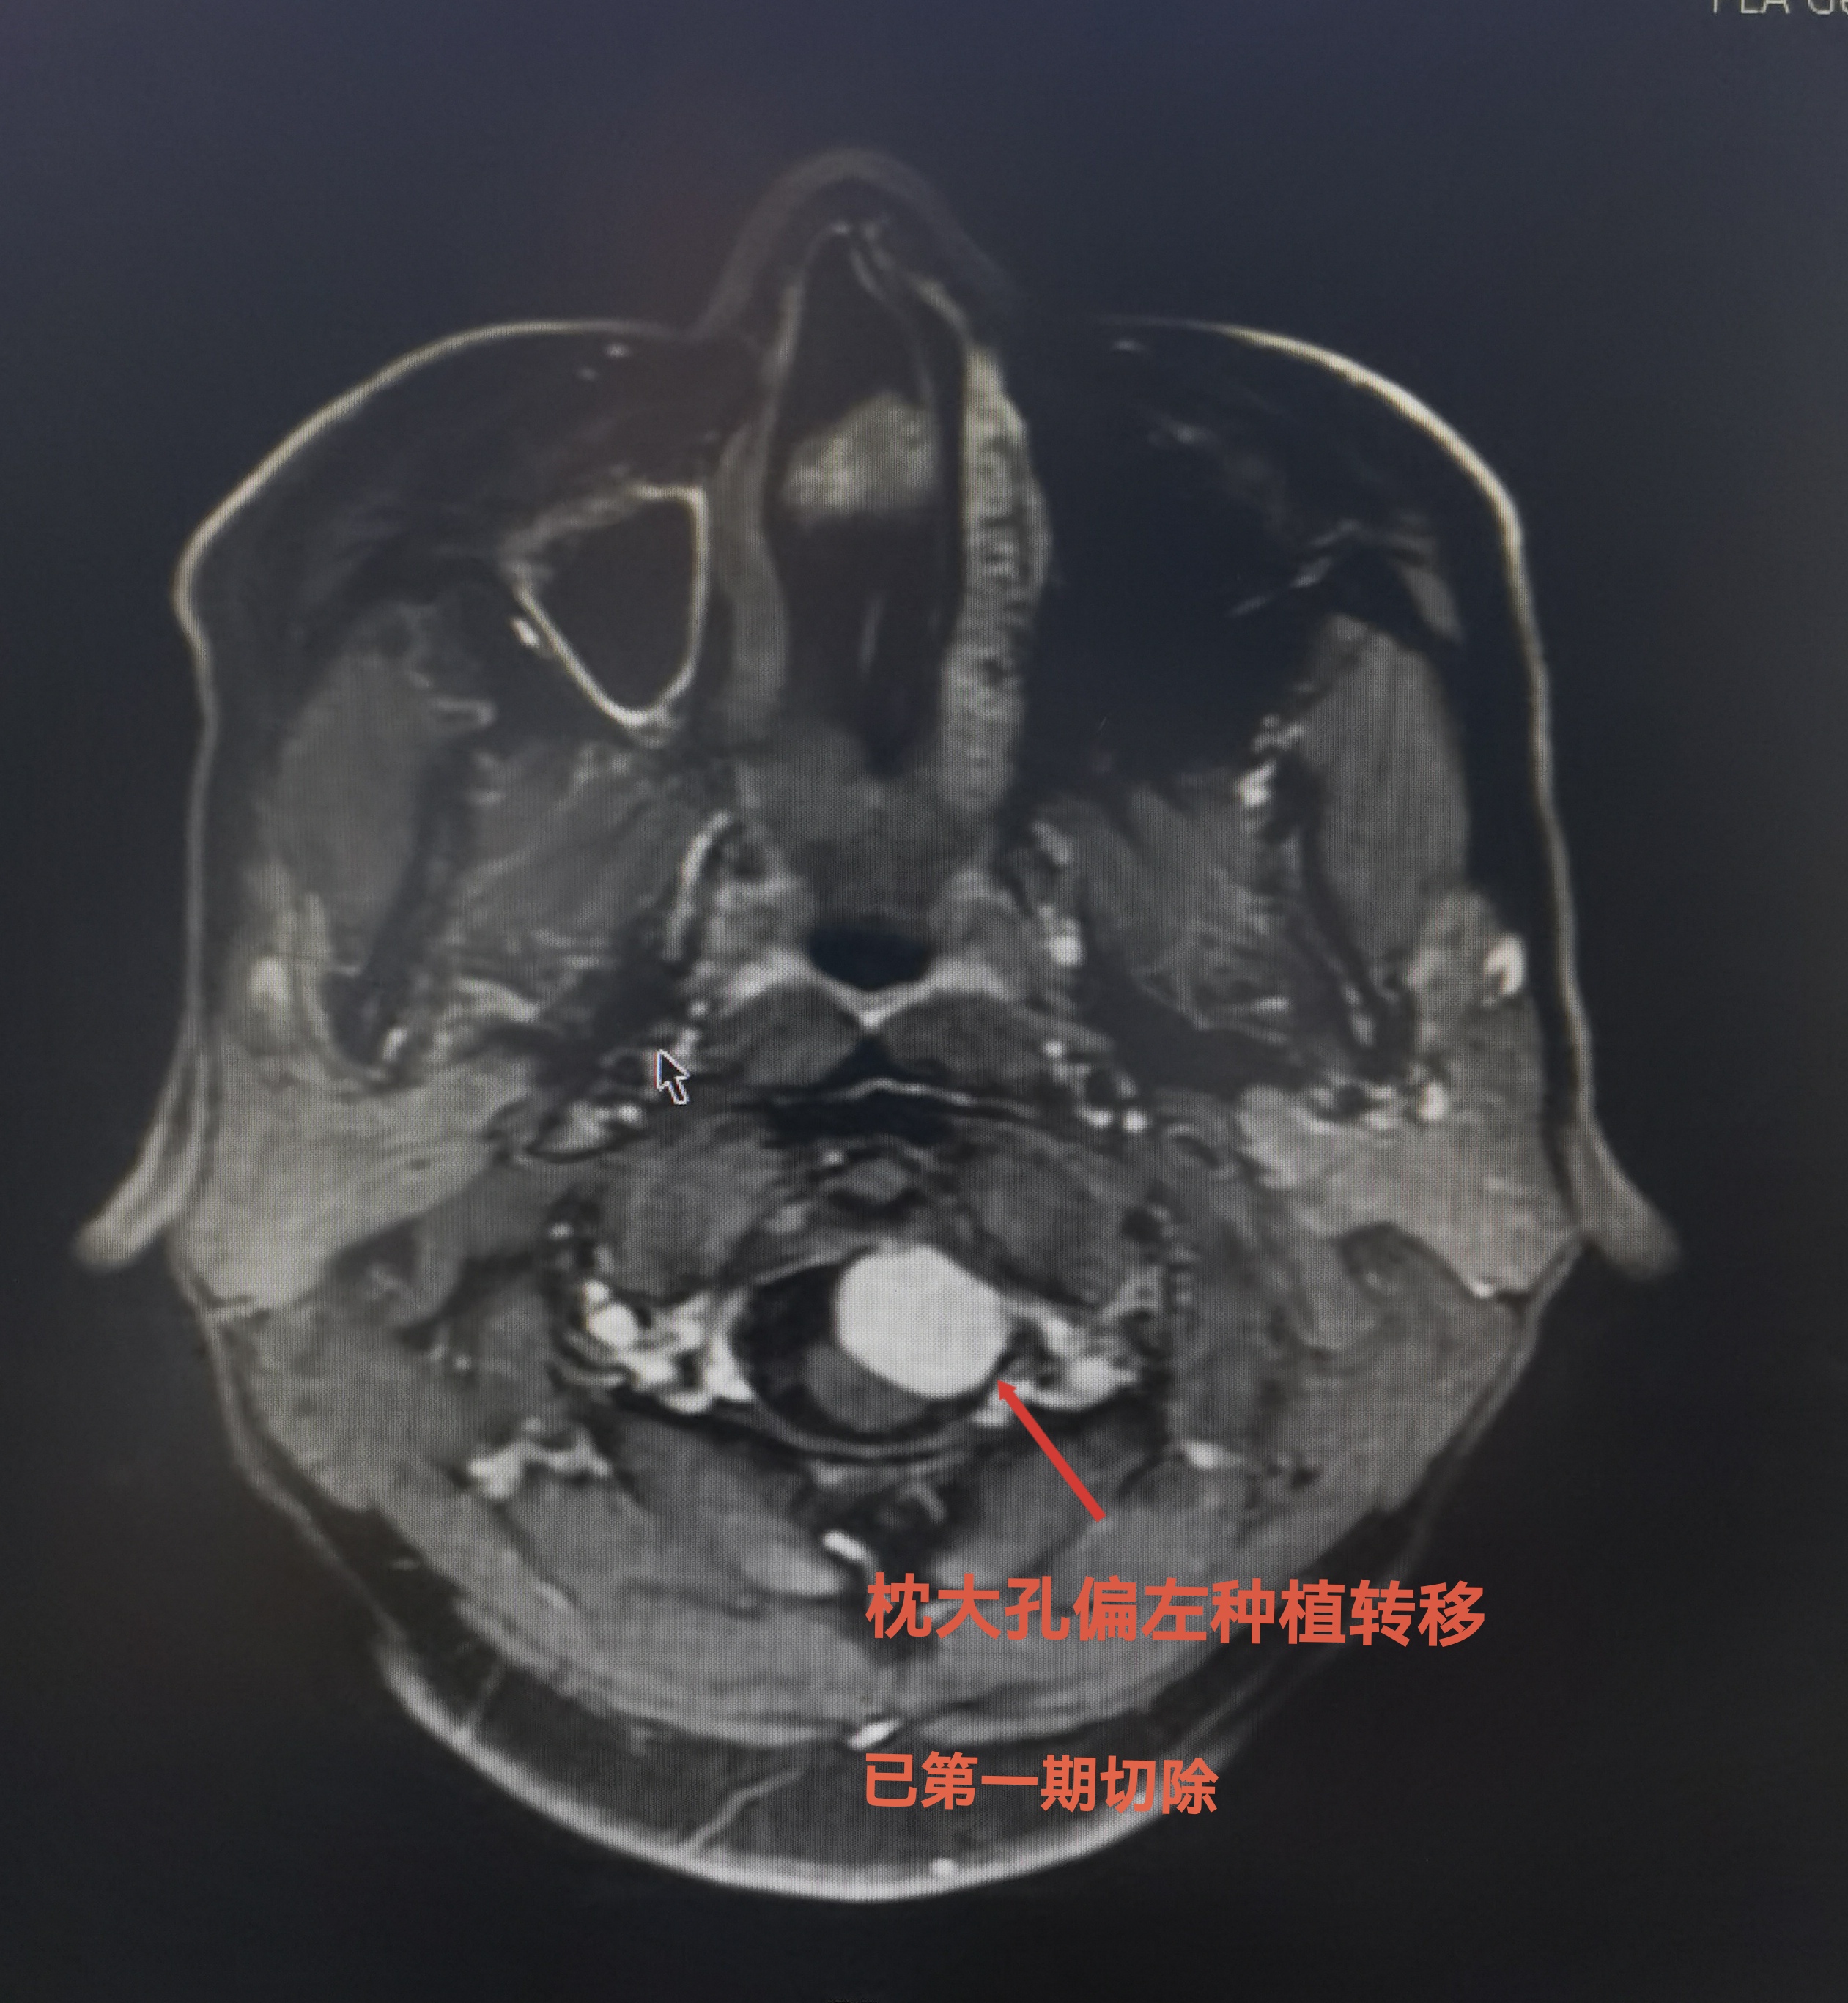

第一次手术,远外侧入路切除枕大孔区肿瘤。病理报告为嗅母。

枕大孔区种植转移,挤压脑干。已于6周前切除。